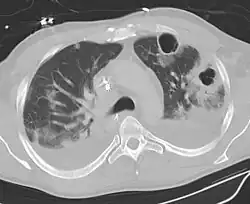

| Computed tomography (CT) scan of chest showing bilateral pneumonia with abscesses, effusions, and caverns. 37-year-old male. | |

Lung abscesses are often on one side and single involving posterior segments of the upper lobes and the apical segments of the lower lobes as these areas are gravity dependent when lying down. Presence of air-fluid levels implies rupture into the bronchial tree or rarely growth of gas forming organism.